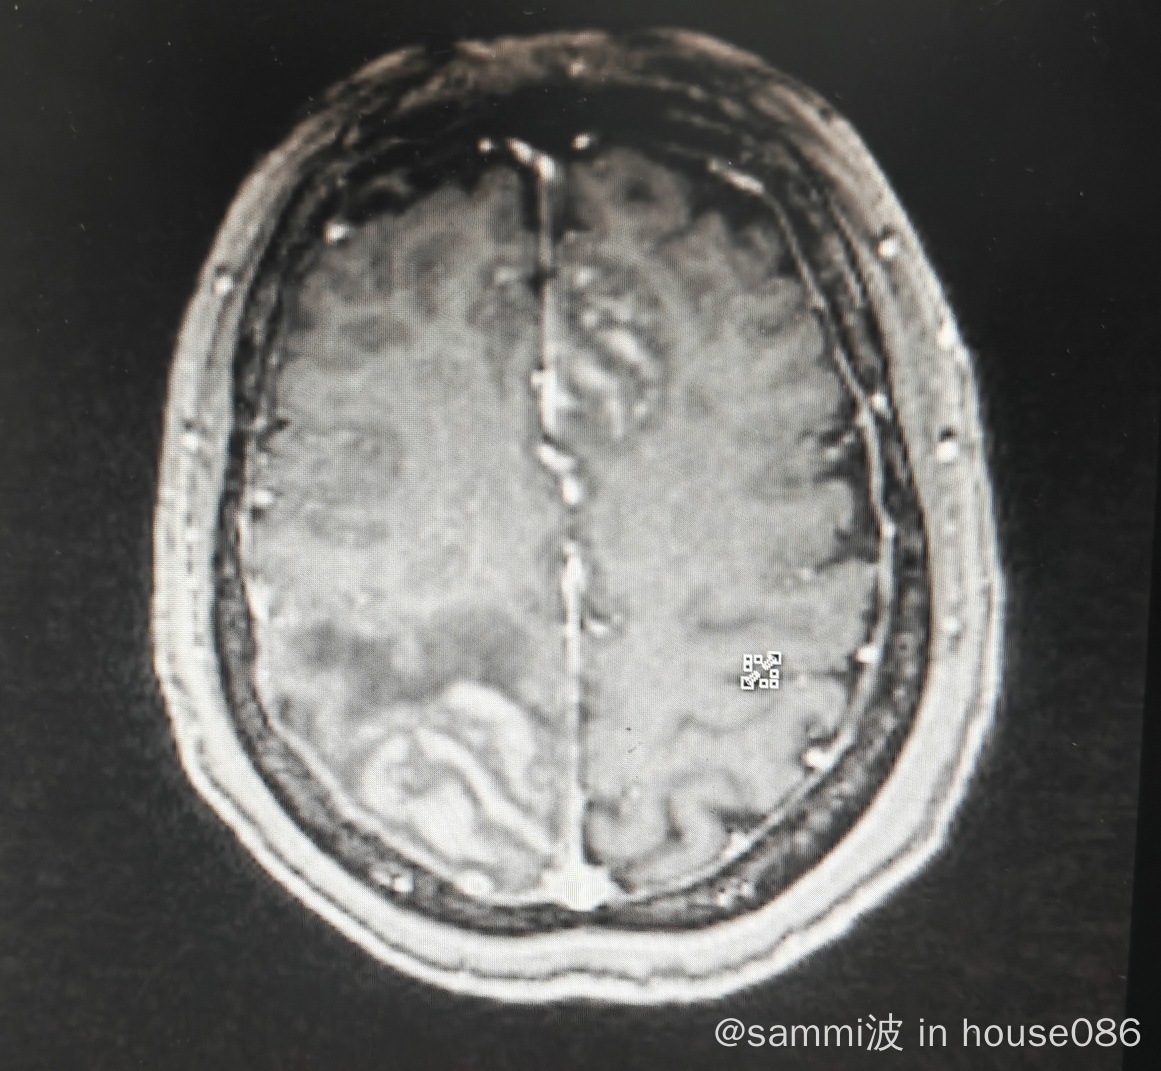

原发中枢弥漫大b细胞

两年前经过MAX+BTK的联合治疗,起码在四个月前的复查时还什么问题都没有呢。刚停药18天,就查到3.6cm的占位,左侧肢体活动受限。